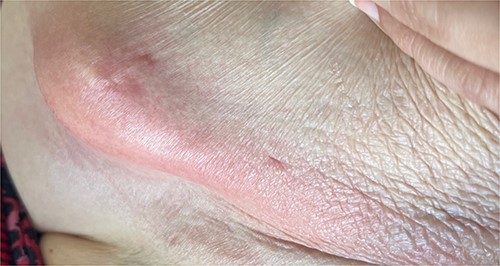

A 65-year-old female with a history of hyperlipidemia, hypertension, hip replacement, lumbar spinal fusion, chronic pain management, and prior laparotomy for endometriosis presented with a 3-day history of nausea, vomiting, and abdominal pain. She had no prior history of diverticulosis or colonoscopy. On examination, she was afebrile and hemodynamically stable. Physical examination revealed left lower quadrant tenderness, swelling, erythema, and fluctuance, suggesting an abdominal wall abscess (Figs 1 and 2). Laboratory tests showed leukocytosis with a count of 24.6 and a positive urinalysis with 2+ leukocytes. A CT scan of the abdomen and pelvis revealed a 3.8 × 3.6 cm air and fluid pocket in the low left anterior abdominal wall, indicative of an abscess likely at the site of a previous drain (Fig. 3). Additionally, there was a 2.8 × 1.8 cm irregular air pocket in the left pelvis, where an abscess had been identified in prior imaging.

CT from readmission with anterior abdominal wall abscess and left pelvic abscess.